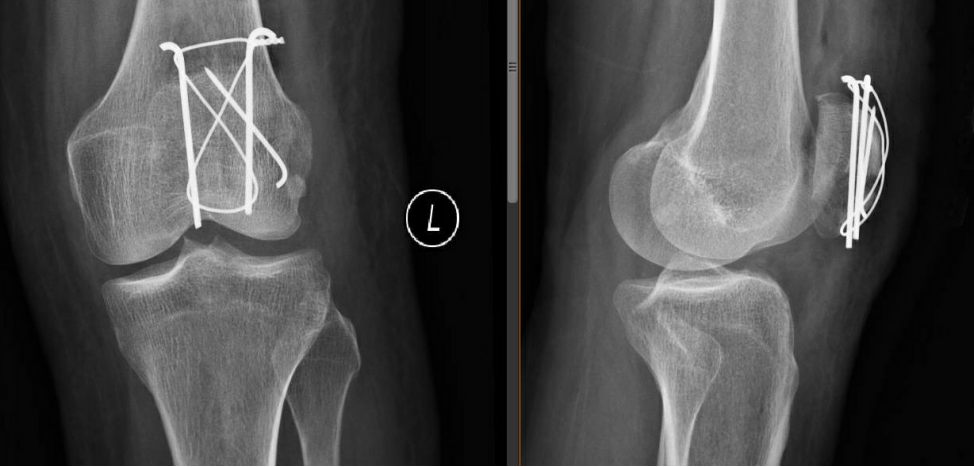

術(shù)后第二天復(fù)查左髕骨X線提示:左髕骨骨折術(shù)后改變,可見(jiàn)金屬內(nèi)固定器影,斷端對(duì)位對(duì)線佳,骨小梁尚規(guī)則,左膝關(guān)節(jié)在位,關(guān)節(jié)間隙尚可。

那如果髕骨骨折了該怎么辦呢?首先要明白髕骨骨折了重要的是要恢復(fù)其關(guān)節(jié)面的平整,關(guān)節(jié)的活動(dòng),恢復(fù)力的傳導(dǎo),關(guān)節(jié)的穩(wěn)定性。所以手術(shù)調(diào)節(jié)就顯得尤為重要。我為本例患者采用了“髕骨骨折切開(kāi)復(fù)位張力帶鋼絲內(nèi)固定術(shù)”進(jìn)行調(diào)節(jié),其主要優(yōu)點(diǎn)在于其符合髕骨生物力學(xué)特點(diǎn)(類(lèi)似尺骨鷹嘴),簡(jiǎn)單可靠,體積小,可使患者早期進(jìn)行功能鍛煉,并且有很高的愈合率。除了這種手術(shù)調(diào)節(jié)方法外,還有其它類(lèi)型的手術(shù),但不管哪種調(diào)節(jié)方式,重要的是,如果不慎髕骨骨折了,就應(yīng)該立刻到醫(yī)院就診進(jìn)行調(diào)節(jié),避免耽誤調(diào)節(jié)時(shí)間。